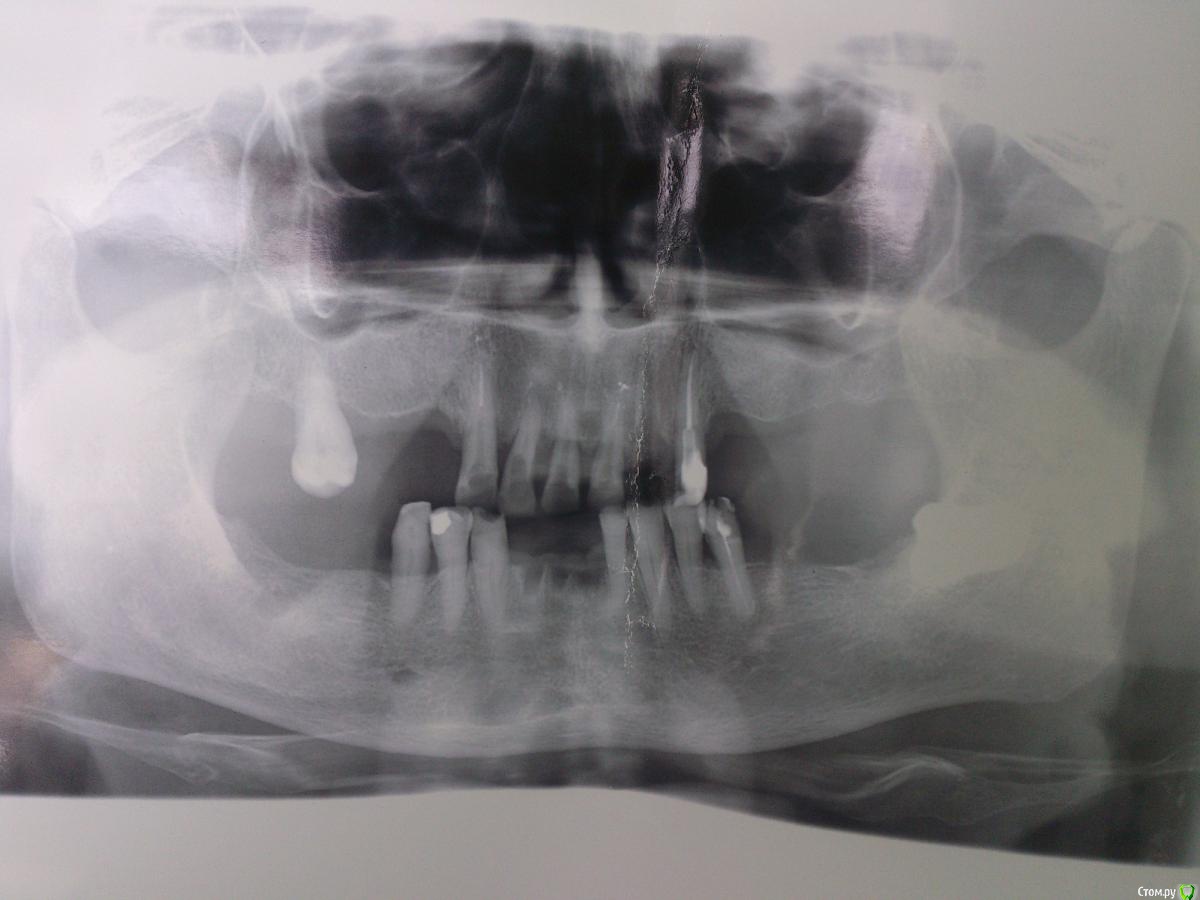

SanderS Опубликовано 16 июня, 2015 Поделиться Опубликовано 16 июня, 2015 Пациентка 1950 г.р. обратилась с жалобами на эстетику и затрудненное пережевывание пищи. 3.1, 4.1, 4.2, 3.7 удалили из-за подвижности , 2.2 так же ушел из-за подвижности и сильного выдвижения.Как быть? В планах: ВЧ - вкладки+МК мост+бюгель замки, НЧ - МК мост+бюгель замки. Сомневаюсь по поводу замков, может лучше опорно-удерживающие? Или вообще рассмотреть имплантацию, но хирург в отпуске, КТ заканчивают ремонт, а пациент просит завершить к концу июля. Ссылка на комментарий

SanderS Опубликовано 22 июня, 2015 Автор Поделиться Опубликовано 22 июня, 2015 оптг Ссылка на комментарий

Школьник из 6Б Опубликовано 22 июня, 2015 Поделиться Опубликовано 22 июня, 2015 А сустав(ы) у пациентки не "щёлкают"? Чтот мне кажется у неё суставные головки смещены к задней стенке суставной ямки. Я бы определил бы тут центральное соотношение челюстей и под него зубные ряды протезировал. Ссылка на комментарий

NazranDantist Опубликовано 23 июня, 2015 Поделиться Опубликовано 23 июня, 2015 оптгВсе убирать, а затем иплантировать. Или делать простые ЧСПП. Не стоит тратить деньги пациента на бюгеля с неизвестным прогнозом. Как раз к концу июля закончите лечение, только в 2016 Ссылка на комментарий

krokomot Опубликовано 23 июня, 2015 Поделиться Опубликовано 23 июня, 2015 Тут тотал делать. Либо обычные сьемники, либо условно-сьемные на имплантах, но что тут оставлять? И, доктор, какой бюгель? Тут по большому счету все на выход. Ссылка на комментарий

Larnary Опубликовано 23 июня, 2015 Поделиться Опубликовано 23 июня, 2015 Эх,чуйка не подвела по атрофии.если денег нет,то я за ЧСПП. 17 бы удалил. Ссылка на комментарий

Паращук Роман Опубликовано 23 июня, 2015 Поделиться Опубликовано 23 июня, 2015 С таким эндодоступами удаленных будет скоро больше. Ссылка на комментарий